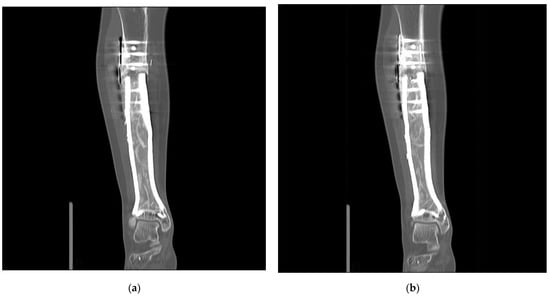

In the four patients—reconstructed using custom-made 3D-printed intercalary megaendoprostheses with a highly cancellous implant surface—distal tibia resection and below-knee amputation were avoided in all cases (Figure 3).

The first patient reconstructed using a highly cancellous 3D-printed monobloc intercalary tibia implant developed an incomplete non-union at the proximal bone-implant interface (Henderson Type 3—structural failure). Two extracortical plates with supplementary interlocking screws bridging the bone-implant interface were used to anchor the implant to the proximal tibial diaphysis without a central stem. This anchorage design was chosen to allow filling the hollow implant body with autologous iliac crest graft (Figure 5). Operative revision and additional plating of the bone implant interface while retaining the original implant were performed 9 months after primary reconstruction (Figure 6). In addition, the ipsilateral fibula was osteotomized and fixed to the tibial column using screw osteosyntheses after roughening the facing bone cortices to encourage bone union. A hypertrophic pseudarthrosis recurred at the tibial bone-implant interface while the fibular transfer consolidated and continues to stabilize the reconstruction by taking part of the load. The patient currently has full weight bearing using a light brace and declines further operative revision as her activities of daily life are not impaired and she has no athletic ambitions. Implant design has been adapted to include a central stem and solid implant body at the proximal bone-implant interface. After this alteration, non-union and hypertrophic pseudarthrosis were avoided in later patients.

Figure 5. Patient #1: Computed tomography scan 43 months after primary reconstruction: (a,b) coronar view of the implant with the depiction of the bone graft-loaded hollow implant cavity and persistent non-union of the proximal implant-bone interface.

Figure 6. Patient #1: Postoperative radiographs after osteosynthetic plating of the proximal implant-bone interface (a) a.p. view; (b) lateral view. R means right.